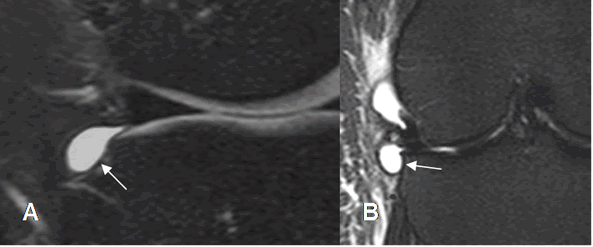

Fig 181. Quiste parameniscal.

A: RM axial en T2 y B: RM sagital en T2. Quiste parameniscal en relación con el cuerno anterior del menisco externo.